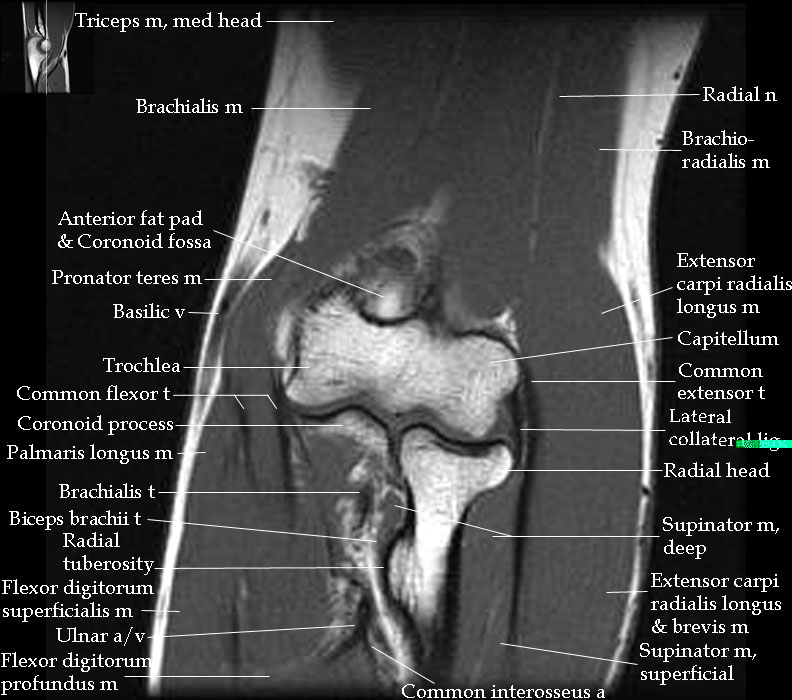

From radiologyassistant.nl

The Radiology Assistant Elbow MRI Radiographic Anatomy Of Elbow this article will discuss the normal anatomy of the elbow and the most common types of elbow pathology as well. 1 article features images from this case. Normal radiographic anatomy of the elbow. the elbow joint is one of the most complex joints in the human body as it incorporates 3 articulations within its joint. knowledge of. Radiographic Anatomy Of Elbow.